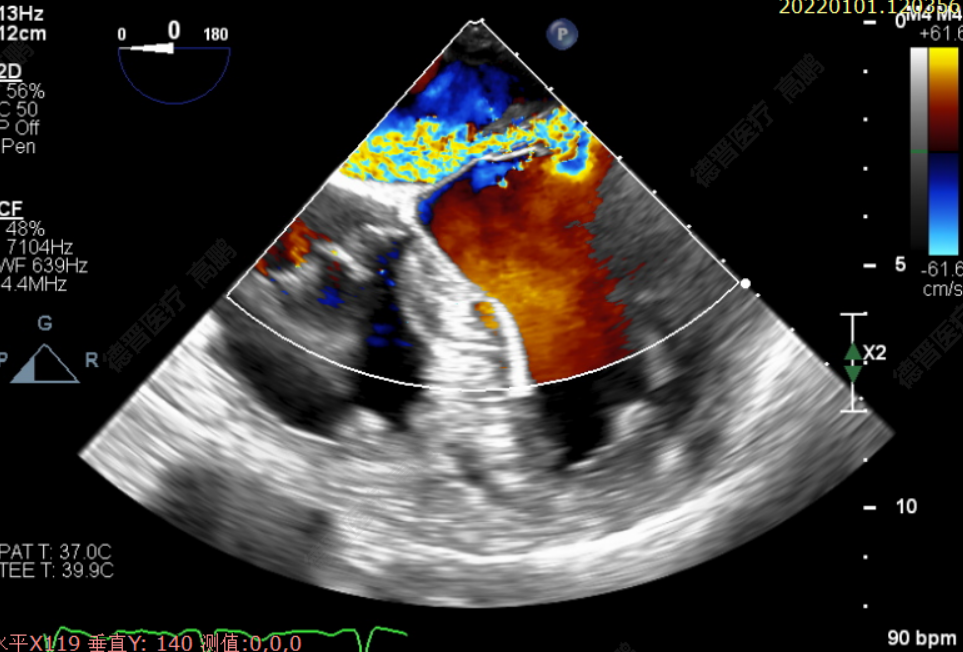

患者为72岁老年男性,反复胸闷、气促1年,加重1周就诊福建省立医院。心脏彩超提示:二尖瓣前叶脱垂伴返流4+;食道超声心动图提示:为二尖瓣后叶A1区偏前联合交界处重度脱垂伴返流4+。既往有COPD(肺功能提示重度阻塞性通气功能障碍)、高血压病病史。